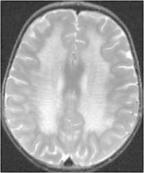

• 異染性腦白質營養不良

628健康網為您分享有關異染性腦白質營養不良的癥狀,異染性腦白質營養不良的治療方法,異染性腦白質營養不良的預防知識...